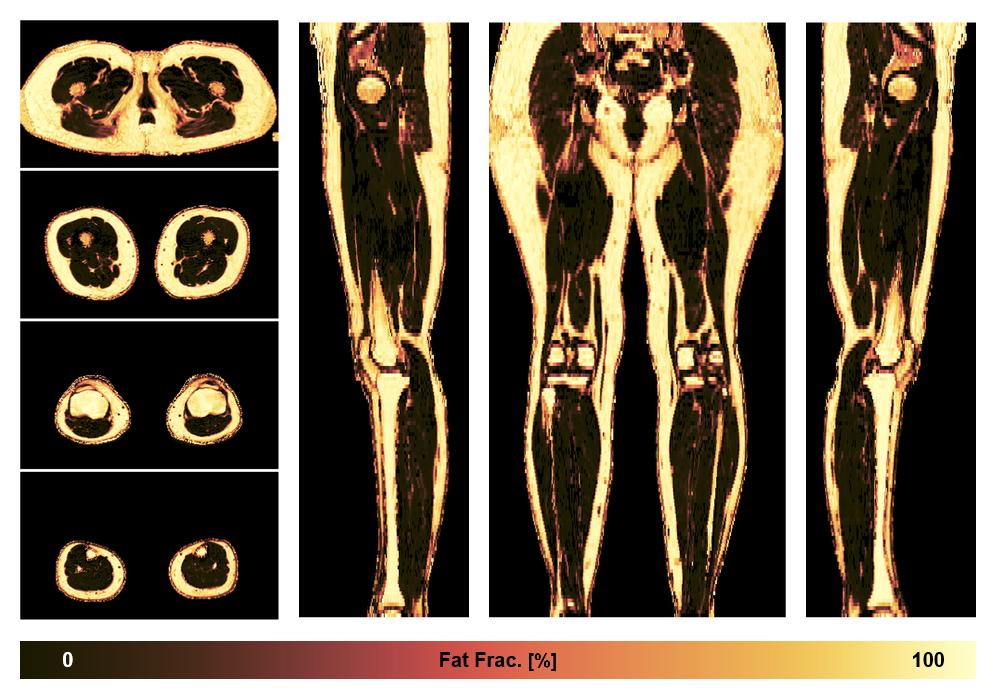

• Fat fraction

The fat fraction of the lower extremity obtained from the dixon reconstruction for muscle water fat quantification.